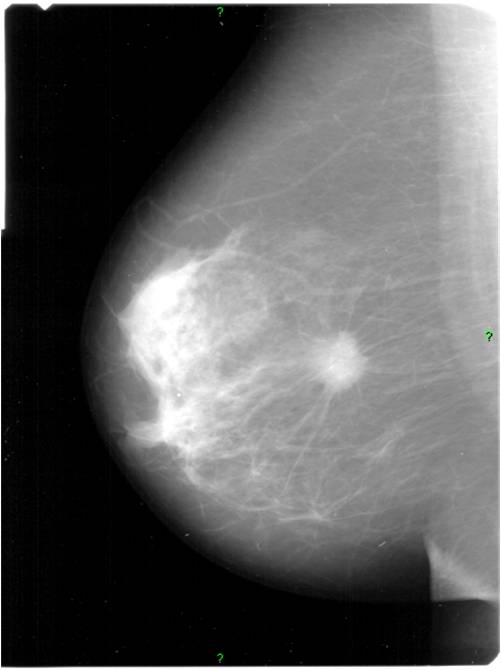

2. Digital mammography has displaced the analogue technic for today almost everywhere: (pictures 1,2,3) phosphorous plate or direct digital methods. For breast imaging the latter is the method of choice. Phases of image production separate. The image is produced on the detectors, but appears on the high resolution monitor and can be stored as a digital data set at various storage mediums (e.g.: CD, hard disk drives).

Image

Picture 1.

Picture 2.

Picture 3.